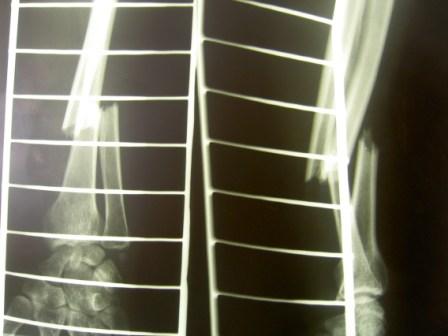

Re: Оцифровка рентгенснимков

послал Михаил 11 Декабрь 2008, 23:27

В анамнезе была попытка работать со сканером, не очень удобно, и для получения хорошего качества изображения необходим сканер хорошей разрешающей способности. и самое главное наилучшие результаты достигаются с применением сканеров проходящего света, а не отражающие (много помех), т.к. снимки тоже зачастую имеют артефакты и низкое качество. Последние 3 года испльзуем негатоскоп и цифровой аппарат Lumix Panasonik 7,0 мегапикселей. Снимаем в режиме макросъёмки без вспышки